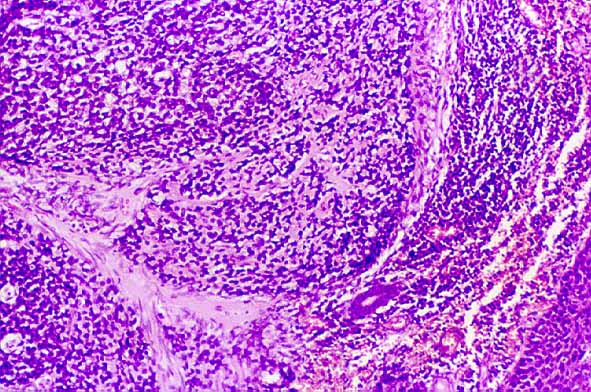

Figura 1. Nidos de células basaloides que muestran depósitos intercelulares de material de tipo membrana basal. Se aprecia ademas carcinoma in situ en superficie (H E, x 40).

Figura 2. Nidos de células basaloides con empalizada periférica y necrosis de tipo comedocarcinoma (H E, x 40).